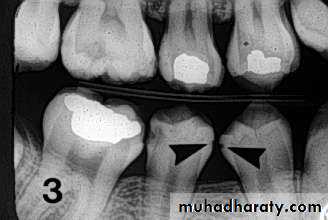

• Radiography

Carious lesions are detectable radiographically when there has been enough demineralization to allow it to be differentiate from normalThey are valuable in detecting proximal caries which may go undetected during clinical examination.

On average they have around 50% to 70% sensitivity in detecting carious lesions.

40% demineralization is required for definitive decision on caries